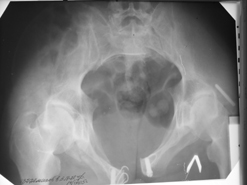

Диагноз : Сочетанная травма. ЗЧМТ. Перелом свода черепа. Ушиб головного мозга.Разрыв лонного и крестцово-подвздошного сочленений с нарушением целостности тазового кольца, с массивной забрюшинной гематомой и пропотеванием в брюшную полость. Перелом 10 ребра справа, осложненный гемопневмотораксом справа, правосторонней пневмонией на фоне ушиба правого легкого. Шок 3-4 ст. Больной поступил в отделение 07.03.2005г. в 16.00 в экстренном порядке через 30 минут после автодорожной травмы.Доставлен КСП. При поступлении состояние больного крайне тяжелое, явления травматического шока, А/Д-80/60 мм.рт. ст. ЧСС-120.В экстренном порядке поднят в операционную, интубирован, совместно с диагностическими мероприятиями лечение шока.При осмотре выявлены перелом 10 ребра справа, разрыв лонного и правого крестцово-подвздошного сочленений. Имеется линейный перелом теменной и височной костей слева с переходом на основание. Диагностическая лапароскопия 07.03.2005г. в 16.30-массивная забрюшинная гематома малого таза.Оставлена контрольная, дренажная трубка.Учитывая кровь в моче произведена цистография - данных за разрыв мочевого пузыря не найдено. Больной переведен в реанимационное отделение.За 08.03.2005г. из брюшной полости выделилось до 1500,0 мл, крови, часть крови реинфузирована. 08.03. в 06.30 наложен торокоцентез справа,удалено 100,0 мл. крови и 200,0 мл. воздуха .. Учитывая продолжающеееся кровотечение в брюшную полость из перелома костей таза, для исключения возможного разрыва внутренних органов 09.03.2005г. произведена Видеолапароскопия., на которой повреждения органов брюшной полости не выявлено.Одновременно произведен шов лонного сочленения проволокой и винтами, с одномоментным наложением стержневого аппарата на кости таза, с целью уменьшения кровотечения из разрывов тазовых сочленений, дренирование гематом. В последующем состояние больного оставалось тяжелым. 10.03.наложена нижняя трахеостома.Далее неоднократно производилась лечебно-диагностическая ФБС.С 10.03 выявлена правосторонняя плевропневмония. КТ головного мозга от 10.03-субарахноидальноекровоизлияние.Срединные структуры не смещены. КТ-контроль от 15.03-открытая моновентрикулярная гидроцефалия4 желудочка. Полисинусит. Постепенно состояние больного медленно прогрессировало к улучшению.С 24.03 переведен на самостоятельное дыхание, а 09.03 переведен в травматологическое отделение.Аппарат стержневой снят из-за перелома стержня (раскрутил больной самостоятельно).После госпитализации в наше отделение проведено дополнительное обследование Рентгекнография, КТ.Хотелось бы услышать Ваше мнение о дальнейшей тактике.-- С уважением, Leonid

Углядел билатеральное повреждение таза. Имеется вертикальная нестабильность со стороны перелома боковой массы крестца, ротационная с контрлатеральной стороны - чрезподвздошный разрыв кп сочленения. Разрыв лона, запирательные отверстия вроде целы.

DS. на сегодняшний день: Вертикальная двусторонняя нестабильная деформация таза, неправильно срастающийся перелом боковой массы крестца слева, срастающийся перелом крыла правой подвздошной кости, застарелый частичный разрыв правого кп сочленения, застарелый разрыв лонного сочленения.